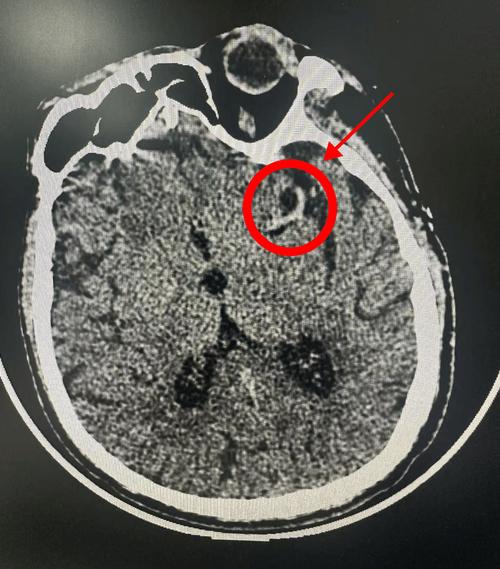

简单直接的回答是:是的,做脑CT检查正常,仍然有可能患有脑梗,尤其是在发病的早期。

小结:如果你在刚发病(特别是6小时内)就去做CT,结果很可能是“正常”的,但这不代表你没有脑梗。

- 梗死灶太小:如果梗死的范围非常小(即所谓的“腔隙性脑梗死”),尤其是在脑干的深处,普通CT可能难以分辨,会被正常脑组织掩盖。

- 梗死灶位置特殊:某些部位的梗死,特别是小脑或脑干的梗死,在常规的头部CT平扫中可能不典型,容易漏诊。